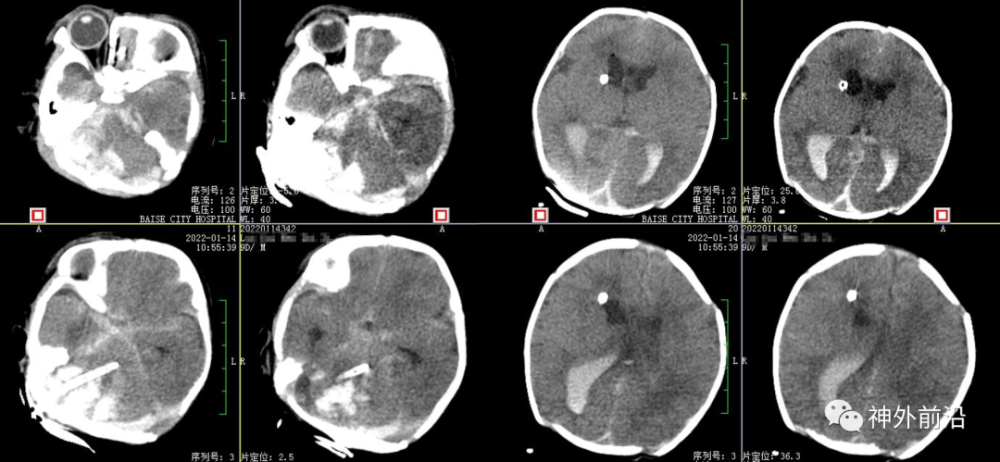

6.术后15小时复查CT,术中抽吸血肿

7.术后2天复查CT,血肿部分清除及退管

8.术后4天复查CT,血肿大部分清除及拔管